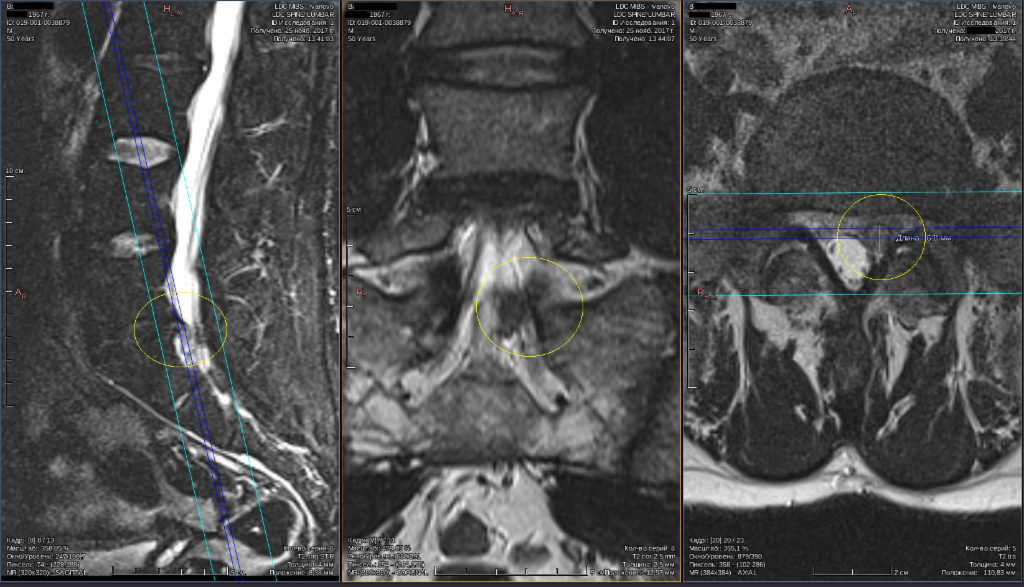

Грыжа Диска L5 S1 Фото

Грыжа Диска L5 S1 Фото 108 фотографий